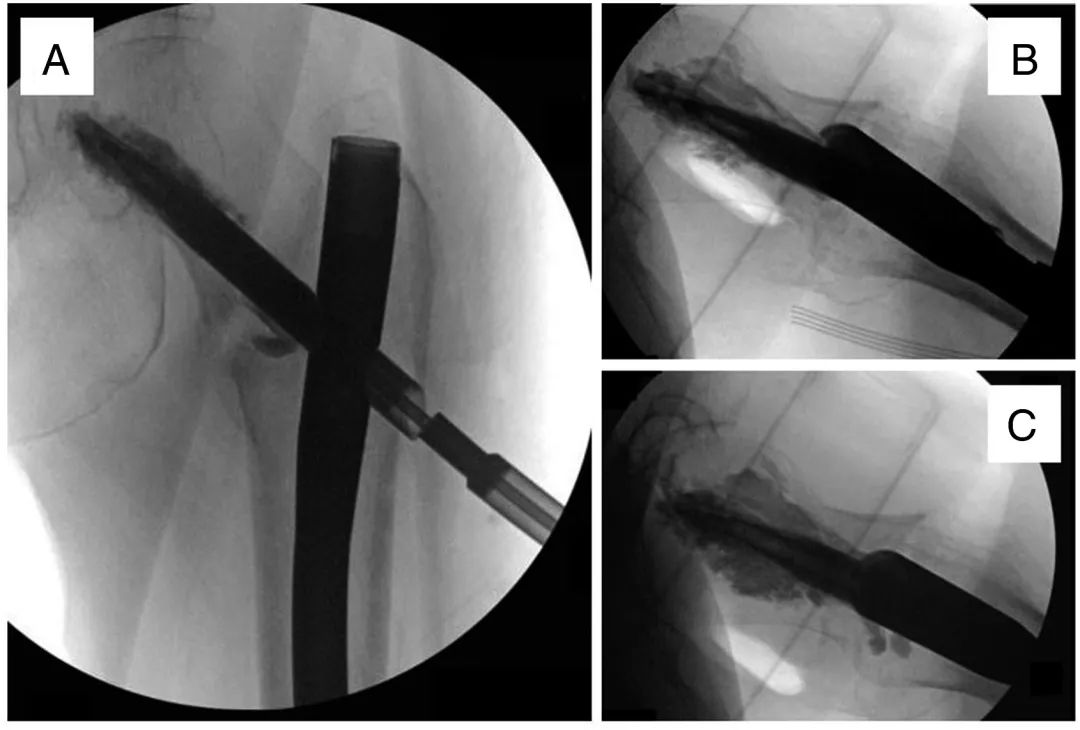

Наконец, головка бедренной кости заполняется костным цементом с помощью инъекционной системы костного цемента (рис. 6).Следует соблюдать осторожность, чтобы избежать экструзии в сустав, используя рентгенограммы в реальном времени и регулируя глубину и ориентацию цементной канюли.

Рисунок 6. Изображение, показывающее первоначальное увеличение количества цемента (A), постепенное заполнение (B) до заполнения дефекта головки бедренной кости (C).